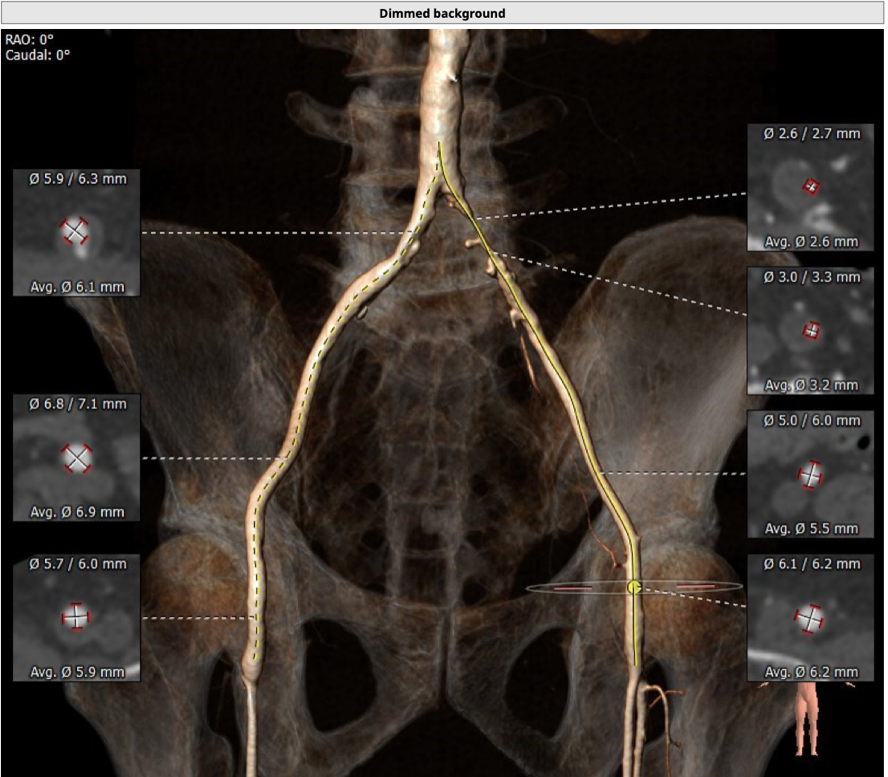

患者为73岁老年男性。CT评估显示其为三叶瓣,伴有轻度钙化,双冠高度可,升主动脉未见明显增宽,主动脉弓部角度平缓。瓣环最短径为17.6mm,最长径为24.7mm,平均瓣环直径为21.1mm。升主动脉平均直径33.6mm。左冠开口高度12.0mm,右冠开口高度14.2mm,冠脉阻塞风险低。外周血管未见明显钙化,最窄处直径为5.7mm。入路情况较佳。

外周血管入路

结合CT分析,李自成教授团队考虑使用右侧股动脉做为主入路,由于左侧髂总动脉近腹主动脉分叉处局部狭窄,考虑副路选择桡动脉;拟选用VenusA-Plus 26型号瓣膜植入。